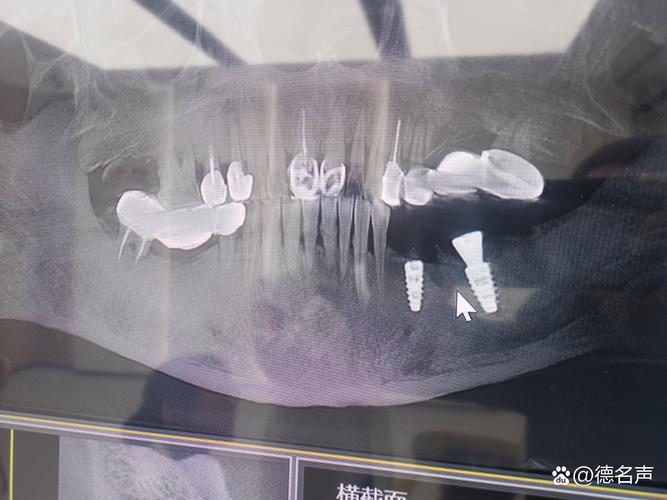

- 骨量(高度和宽度): 种植体需要植入足够的骨组织中才能稳固,X光(尤其是全景片和CBCT)能精确测量牙槽骨的高度、宽度和密度,判断是否足够容纳种植体。

- 下牙槽神经管: 在下颌后牙区,种植体必须避开下牙槽神经,否则会导致下唇、下巴麻木甚至永久性损伤,X光能清晰显示神经管的位置和走向。

- 上颌窦: 在上颌后牙区,种植体不能穿入上颌窦,X光能显示上颌窦底的位置、大小和形态,帮助医生确定种植体植入的安全深度和位置。

- 邻牙牙根: 确保种植体不会损伤邻牙的牙根。

- 基于X光提供的三维信息(尤其是CBCT),医生可以:

- 精确选择合适尺寸、长度、直径的种植体。

- 确定最佳的植入角度和深度。